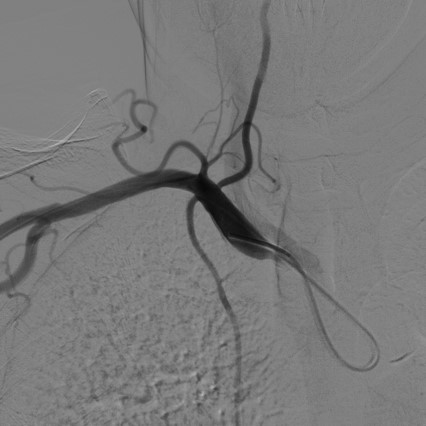

导管超选择右颈动脉